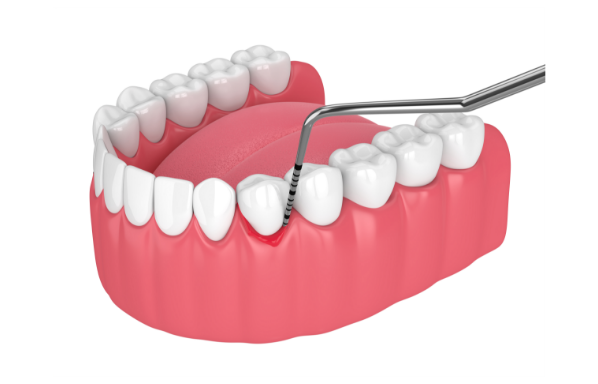

数値で管理する「見える予防」

• 歯周ポケット検査(歯と歯ぐきの間の溝の深さ)

• BOP(歯周ポケットを検査する際に出血があるかどうか)

歯周ポケットは「歯周病の進行度」を示し、BOPは「歯ぐきの炎症の程度(活動性)」を示す重要な指標です。特にBOPが高い状態は「歯周病・虫歯の進行リスクが高い状態」を意味します。

当院ではBOP10%以下にコントロールすることを一つの目標とし、状態の変化を継続的に評価していきます。

必要に応じてPCR(プラーク付着率)も測定し、より精密な管理を行います。